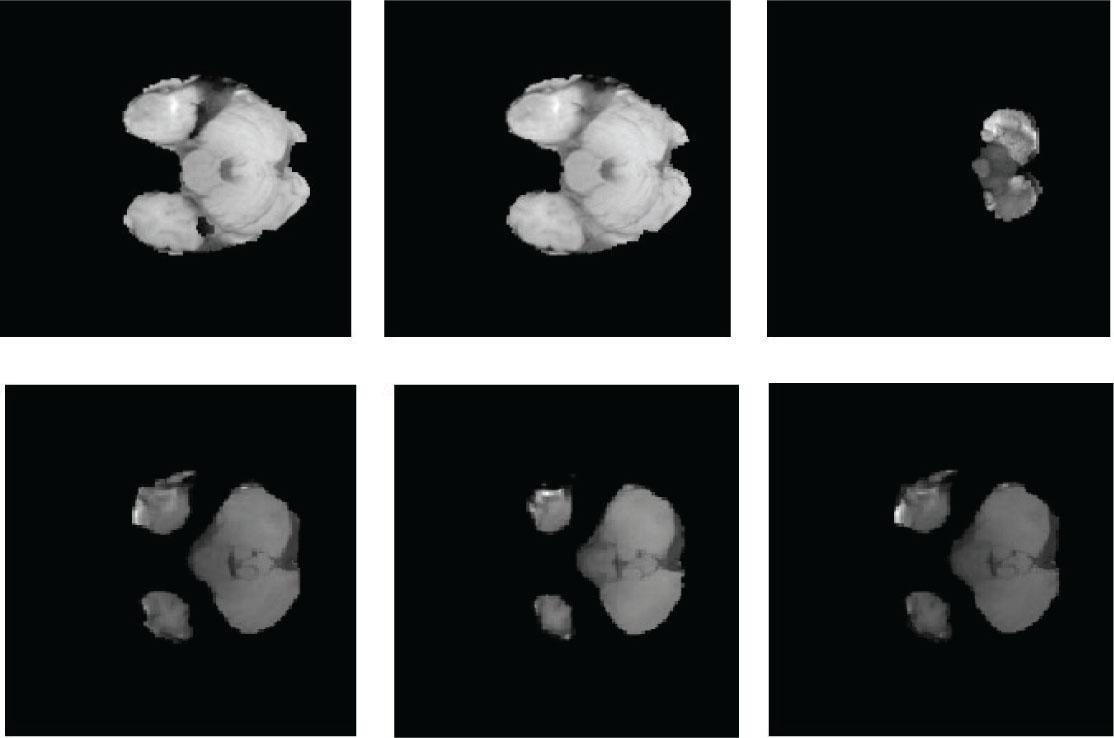

Figure 7 represents the local features gained after LTcp over various sets of MRI images.

Illustration of (A) local features from T1 MR images and (B) local features from T2 MR images. (C) Local features from the FLAIR MR image.